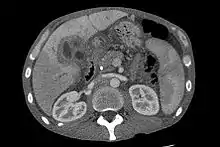

Ultrasound of the liver and biliary tree is often used as the initial imaging modality in people with suspected obstructive jaundice.[49][50] Ultrasound can identify obstruction and ductal dilatation and, in some cases, may be sufficient to diagnose cholangiocarcinoma.[51] Computed tomography (CT) scanning may also play an important role in the diagnosis of cholangiocarcinoma.[52][53][54]

While abdominal imaging can be useful in the diagnosis of cholangiocarcinoma, direct imaging of the bile ducts is often necessary. Endoscopic retrograde cholangiopancreatography (ERCP), an endoscopic procedure performed by a gastroenterologist or specially trained surgeon, has been widely used for this purpose. Although ERCP is an invasive procedure with attendant risks, its advantages include the ability to obtain biopsies and to place stents or perform other interventions to relieve biliary obstruction.[12] Endoscopic ultrasound can also be performed at the time of ERCP and may increase the accuracy of the biopsy and yield information on lymph node invasion and operability.[55] As an alternative to ERCP, percutaneous transhepatic cholangiography (PTC) may be utilized. Magnetic resonance cholangiopancreatography (MRCP) is a non-invasive alternative to ERCP.[56][57][58] Some authors have suggested that MRCP should supplant ERCP in the diagnosis of biliary cancers, as it may more accurately define the tumor and avoids the risks of ERCP.[59][60][61]